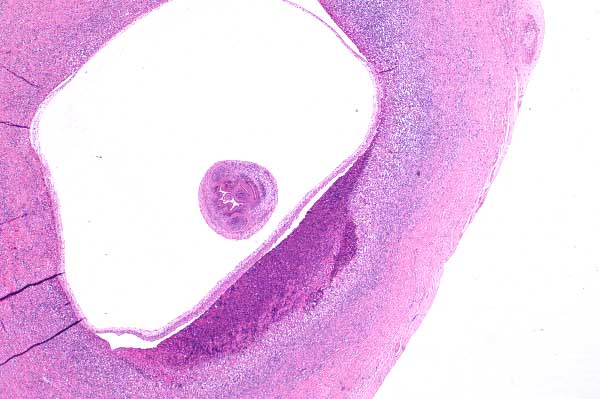

| 2x   |   Hematoxylin and Eosin | ||||

Focally within the myocardium is a metacestode cyst surrounded by a fibrous capsule.